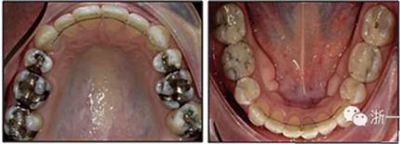

患者曾行正畸治療,現(xiàn)覺(jué)笑容不美觀前來(lái)就診?;颊哒嬗^及側(cè)貌示下頜發(fā)育不足,偏高角,唇閉合不全。上下頜中線齊。覆合、覆蓋4毫米。磨牙關(guān)系及尖牙關(guān)系II類。上頜擁擠度4mm,下頜擁擠度6mm。4顆第一前磨牙在第一次正畸治療時(shí)已拔除。上下牙弓呈尖圓型,牙弓狹窄。

患者側(cè)貌改善,下唇唇肌緊張消失,上下唇可自然閉合。磨牙及尖牙關(guān)系糾正至I類,覆合覆蓋正常。上下頜弓型糾正至卵圓形,牙弓寬度增加。頭影測(cè)量分析示SNA角81.8°,ANB角3°。頭影測(cè)量重疊圖示下頜骨向后旋轉(zhuǎn),垂直面高度略有增加。